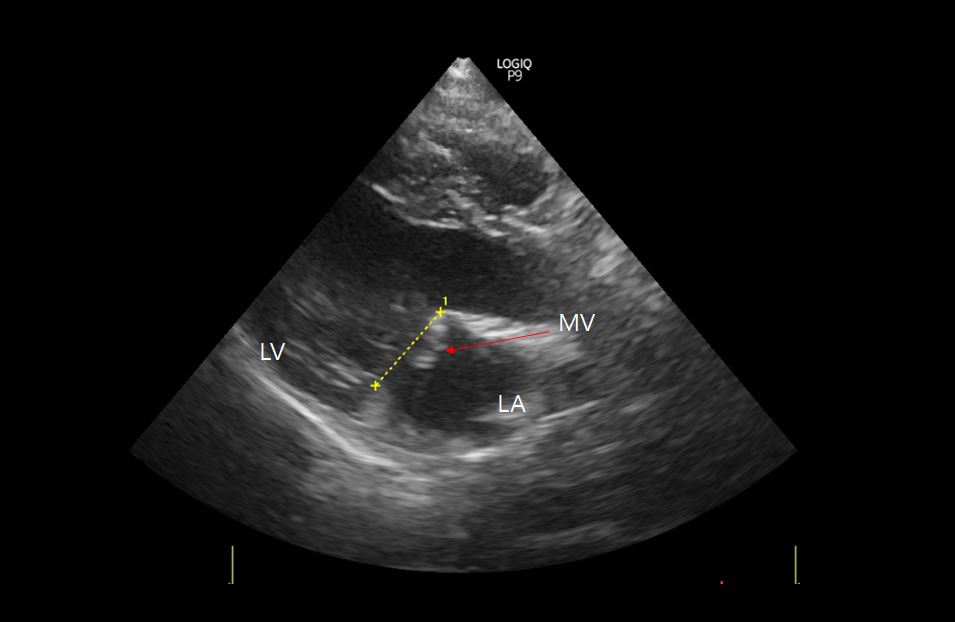

<이첨판막의 변성 및 과도한 움직임>

<좌심방 확장 소견은 보이지 않음>

다음날 수면호흡수 40회 미만으로 안정화 및 호흡 양상이 개선되어 보다 정밀하게 진단하기 위해 추가 검사를 진행했습니다. 심장초음파상 이첨판막의 심한 변성과 함께 수축기에 이첨판이 좌심방 쪽으로 심하게 꺾이는 prolapse 소견을 보였으며 이는 이첨판막을 지지해 주는 건삭의 파열을 의심하게 했습니다.

심장초음파 소견과 함께 환자의 경우 별다른 증상 없이 갑자기 호흡곤란이 나타났다는 점을 고려하여 Partial chordae tendineae rupture(건삭 부분 파열)로 진단하였습니다.